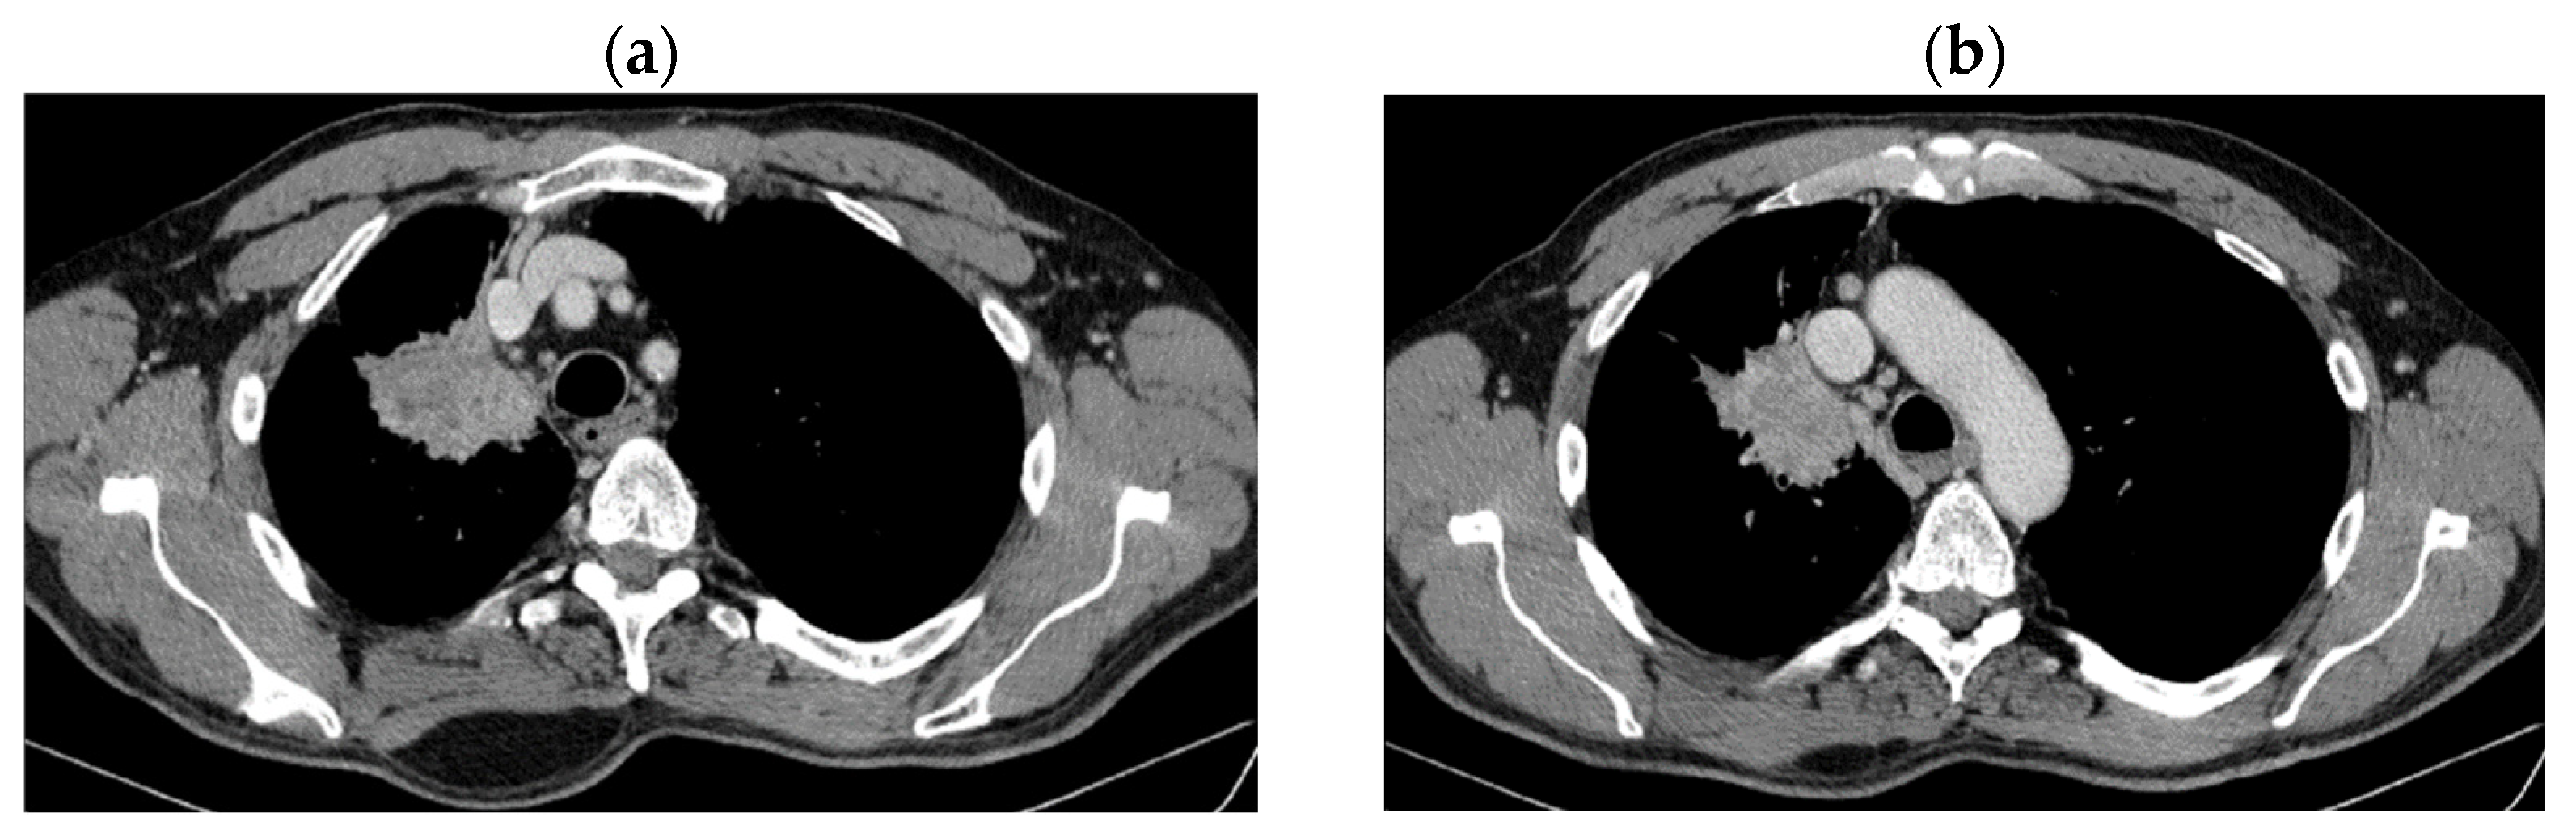

2. Case Presentation

2.1. Systemic Third-Line Therapy (4xDocetaxel) Was Initiated 04–07/2020

2.2. Monitoring 2022: Oncological Commission 1910/16.08.2022

2.3. Oncological Committee 07/25/2023 Recommended